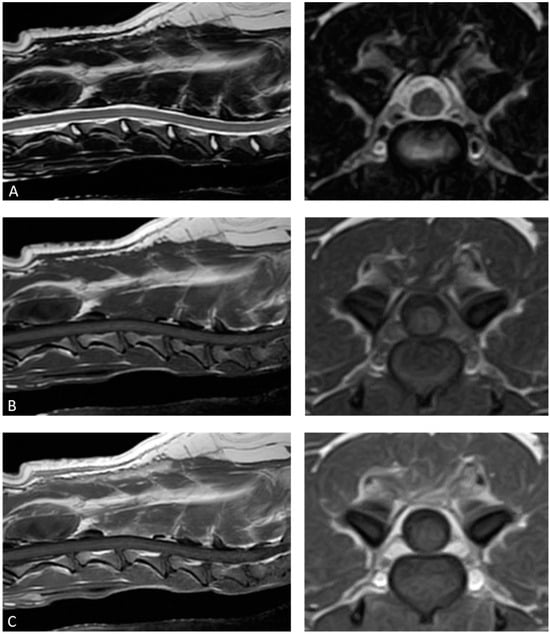

2. Case Description